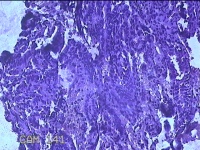

宫颈管内容物

性别

女

年龄

41岁

临床诊断

1.子宫内膜息肉 2.疤痕子宫

一般病史

阴道流血2天。

标本名称

大体所见

灰白暗红色不规则碎组织0.7x0.5x0.2cm一堆。